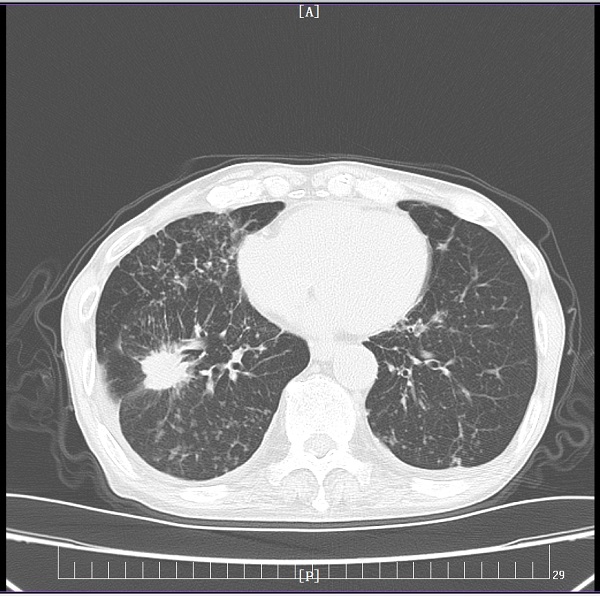

充分研究病情后,刘娟妮主任团队积极与家属沟通,对症治疗的同时,在CT引导下行经皮肺穿刺活检术,术后病理提示:中分化腺癌,基因检测结果提示:EGFR Exon19突变。明确诊断后,刘娟妮主任团队一边安慰患者及家属的情绪,一边对患者的全身状况及疾病进行了充分的评估,邀请相关科室会诊,经MDT讨论并结合患者目前症状、基因检测结果分析及国内外最新指南推荐,制定了个性化的治疗方案,给予口服三代靶向药控制肿瘤。治疗1个月后,复查头颅MRI及胸部CT,结果显示患者肺原发肿瘤、脑多发转移瘤较前均缩小、部分消失。

治疗前

治疗后